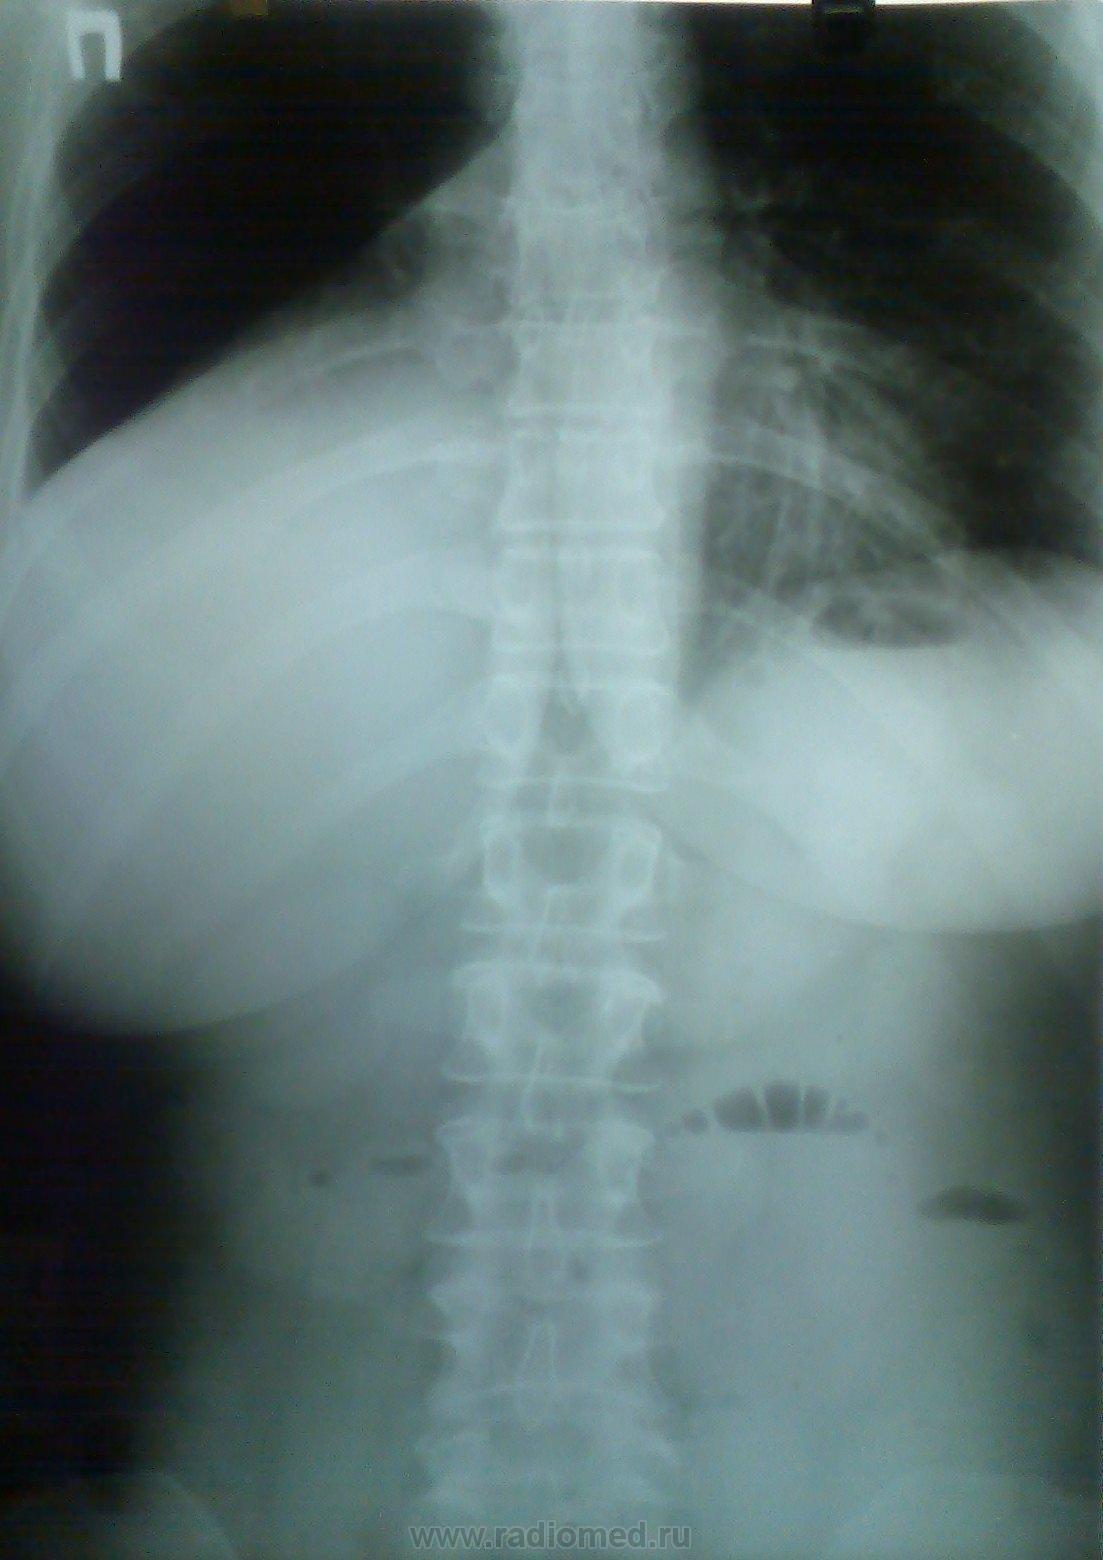

Ну что же начнем помаленьку. Заболела женщина в феврале. Первый снимок датирован 13 марта...... Следующий - 23 марта....

Приложения:

13 мартра - некрасивый правый корень (особенно это видно на правом боковом). + что-то слева. Надо дообследовать.

Потом (на след снимках)  видно уже произошел ателектаз нижней доли справа :(

Ателектаз нижней и средней долей не вызывал у меня сомнения еще на первых рентгенограммах, да простит меня Медея за провокационные вопросы по поводу увеличения доли. Как тут не вспомнить лекции Михаила Абрамовича Гинзбурга.

Слишком явным были изменения, дабы уложить их только в плеврит.

Клинически сейчас только покашливание, небольшая потеря в весе, да СОЭ 65. Вот и все.

Не ухватись я за картину ателектаза, так и ушла бы она домой "покашливать".

Заключение практически слово в слово повторяет Ваше, только я добавил...ателектаз нижней и средней доли...